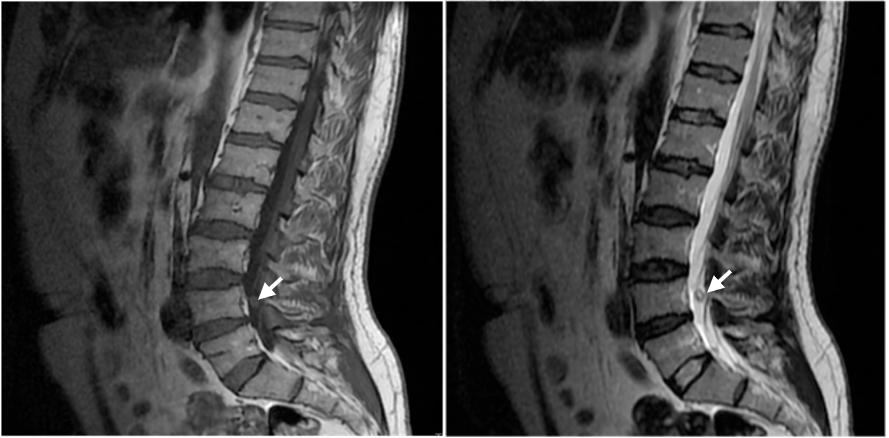

Figure 1: Sagittal T1 weighted image.

Figure 2: Sagittal T2 weighted image.

MRI is the diagnostic modality of choice due to its noninvasive nature and high accuracy on spinal tumours. The critical MRI indicators for spinal schwannomas include:

Signal intensity that is equal or less than that of spinal cord on T1 weighted images and a mild to marked hyperintensity on T2-weighted images. Focal areas of even greater hyperintensity on T2-weighted images often correspond to cystic regions, whereas hypointensity may represent hemorrhage, dense cellularity, or collagen deposition [2.3]. Virtually, 100% enhance on T1 C+.